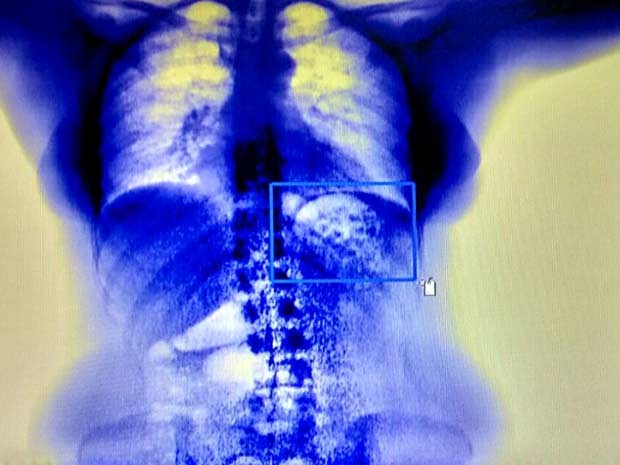

Nove detentos beneficiados com a saída temporária — popularmente conhecida como Saidão — no Dia dos Pais, comemorado no domingo (9), foram flagrados com drogas no corpo na segunda-feira (10) ao retornarem para o Centro de Internamento e Reeducação, na Papuda. Eles vão responder pelo crime de tráfico de entorpecentes em ambiente prisional.

A prisão em flagrante foi um desdobramento da operação Braço Longo da Lei, que teve início na sexta-feira (7) e terminou ontem. Divididos em 45 equipes, 180 servidores lotados no sistema penitenciário intensificaram a fiscalização nesse período. Visitaram 2.456 residências, detiveram 151 apenados por terem descumprido regras estabelecidas pela Vara de Execuções Penais e apreenderam duas armas de fogo e munições.